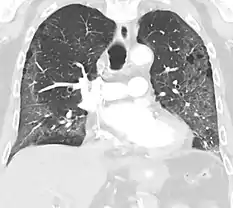

High-Resolution CT image in a patient with Pneumocystis pneumonia infection showing ground-glass opacities.